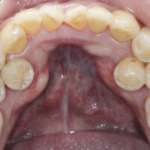

I denti sovrannumerari analizzati con la CBCT

I denti sovrannumerari rappresentano una condizione clinica da studiare con grande attenzione. Per farlo, oggi gli odontoiatri hanno a disposizione una tecnologia molto sofisticata,...